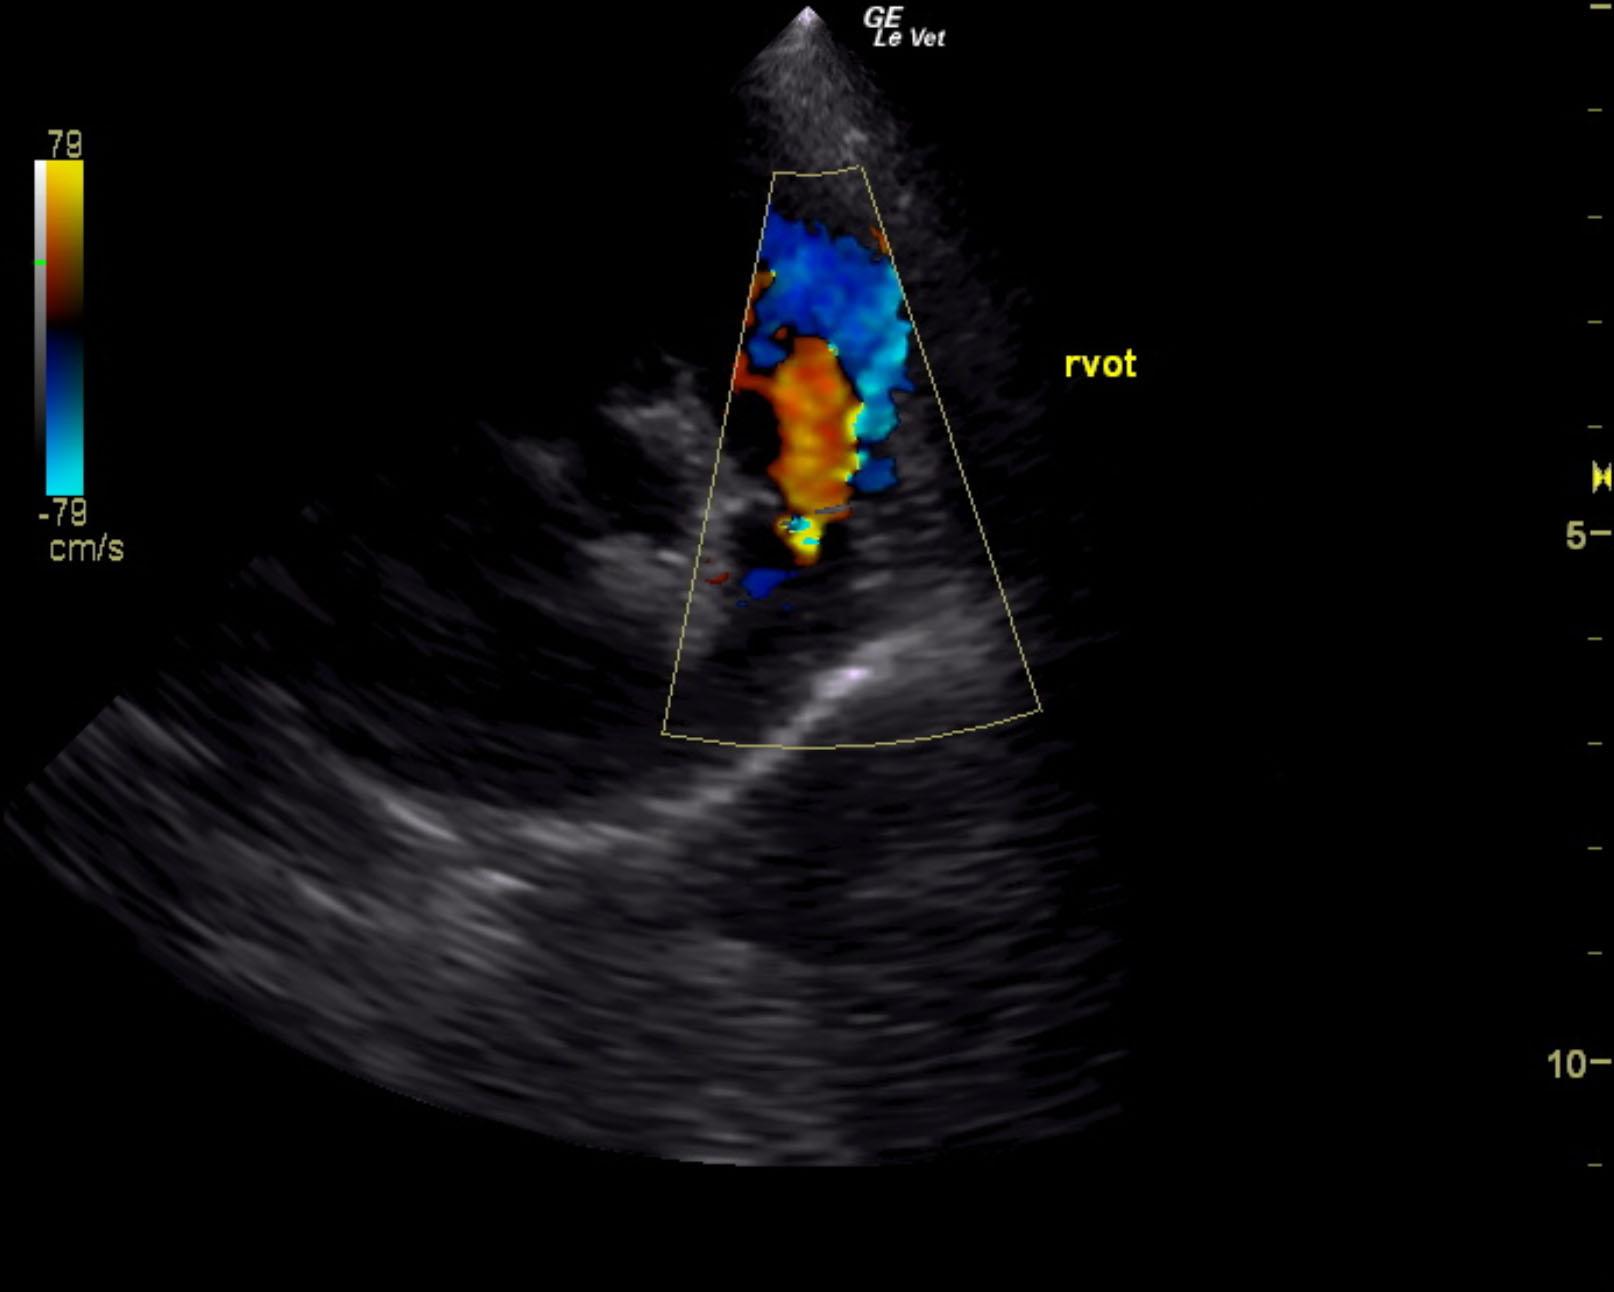

The cardiac presentation revealed moderate left and right sided overload with tricuspid and mitral valve vegetative lesions. Left atrial and right atrial enlargement was noted. Right ventricular overload was noted with flattening of the ventricular septum. Slight prolapse of the anterior mitral valve leaflet was noted. Prolapse of the tricuspid vavle was also noted. Significant pulmonic insufficiency and tricuspid insufficiency was noted. This is consistent with pulmonary hypertension.

Pulmonic insufficiency velocity 1.8 m.sec.